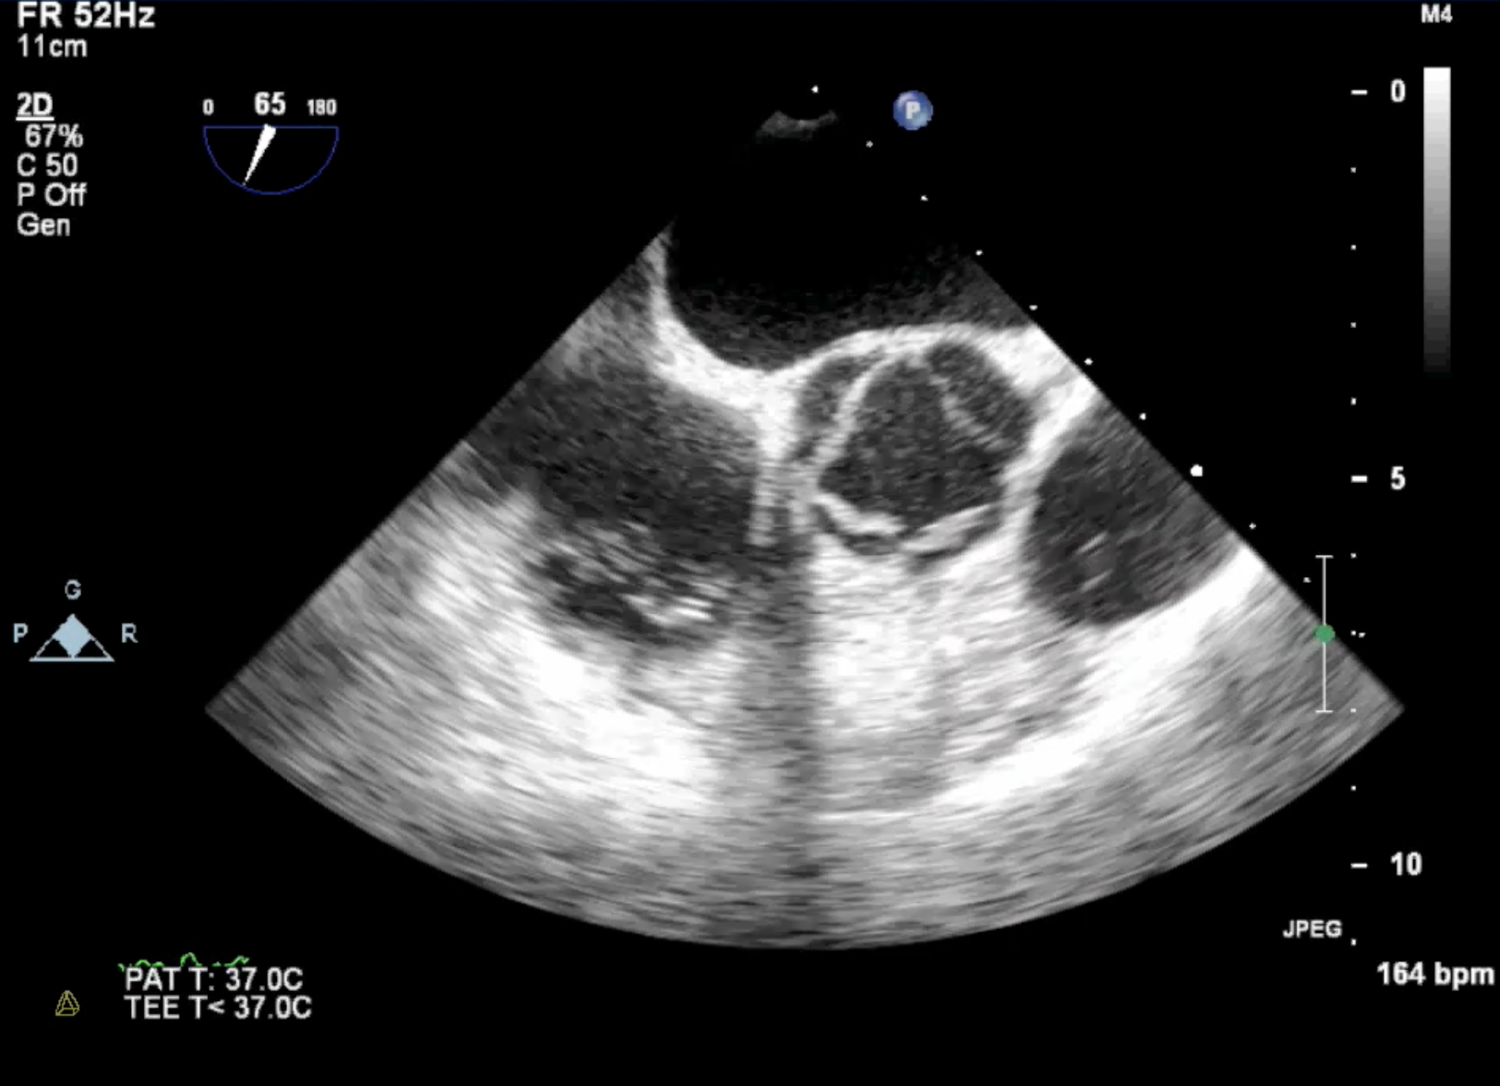

Trans-oesophageal echocardiogram